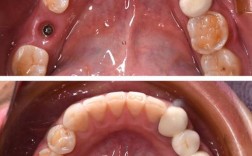

- 患者: 张女士,42岁

- 问题: 上颌右侧门牙(侧切牙)多年前因外伤脱落,一直未能修复,缺牙位置明显,影响美观和咀嚼,也导致邻牙有轻微倾斜。

- 初始状态: 牙槽骨有一定程度的吸收,但医生评估后认为具备种植条件。